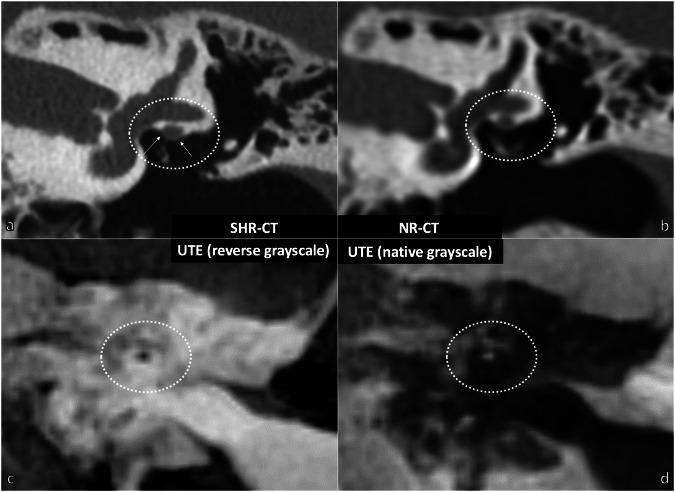

Results: The facial nerve was always clearly visible (score ≥ 2) in the MRI, NR-CT, and SHR-CT scans (p ≥ 0.621). However, the chorda tympani nerve (CTN) was clearly visualized in UTE, STARVIBE, and PETRA sequences in only 33% (2/6 specimens, p = 0.016), 50% (3/6 specimens, p = 0.038), and 83% (5/6 specimens, p = 0.017) of cases, respectively, whereas it was always clearly visualized in SHR and NR-CT (p = 0.426). The round window (RW) was never visualized in MRI sequences (p ≤ 0.010), whereas it was identified in all cases in SHR and NR-CT (p = 1.000). There was a strong correlation between measurements obtained from MRI and CT modalities (ICC ≥ 0.837).

Relevance statement: CT-like MRI sequences can image the anatomy of the facial recess and the length of the basal turn of the cochlea with similar accuracy as conventional CT, although they cannot image the round window.